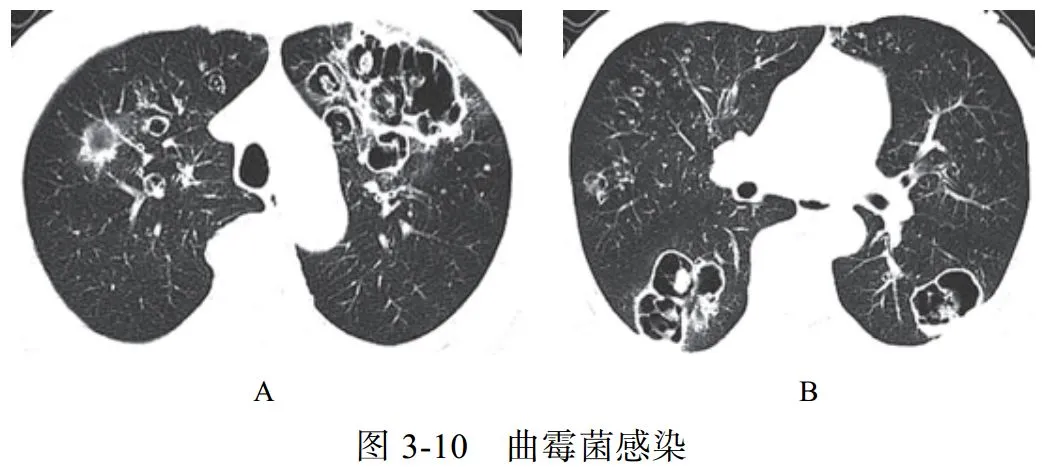

(一)曲霉菌感染

肺曲霉菌病主要是因吸入曲霉菌孢子而发病,是一种机遇性感染,为非化脓性炎症,可寄生于结核性空洞、肺癌空洞,以及慢性肺脓肿、肺囊肿、肺大疱及支气管扩张等病变所致的空洞或空腔内,少数因消化道或上呼吸道曲霉菌感染经血行播散至肺部。曲霉菌的菌丝呈游离状态,形成曲菌球

影像学改变:

(1)典型征象为曲菌球(图 3-10)、空气半月征、手套征

(2)多样化病灶并存,可伴有晕征、空洞、洞丝征及树上挂果征

(3)曲菌球随体位改变而变化,球形内容物一般较光滑,密度均匀